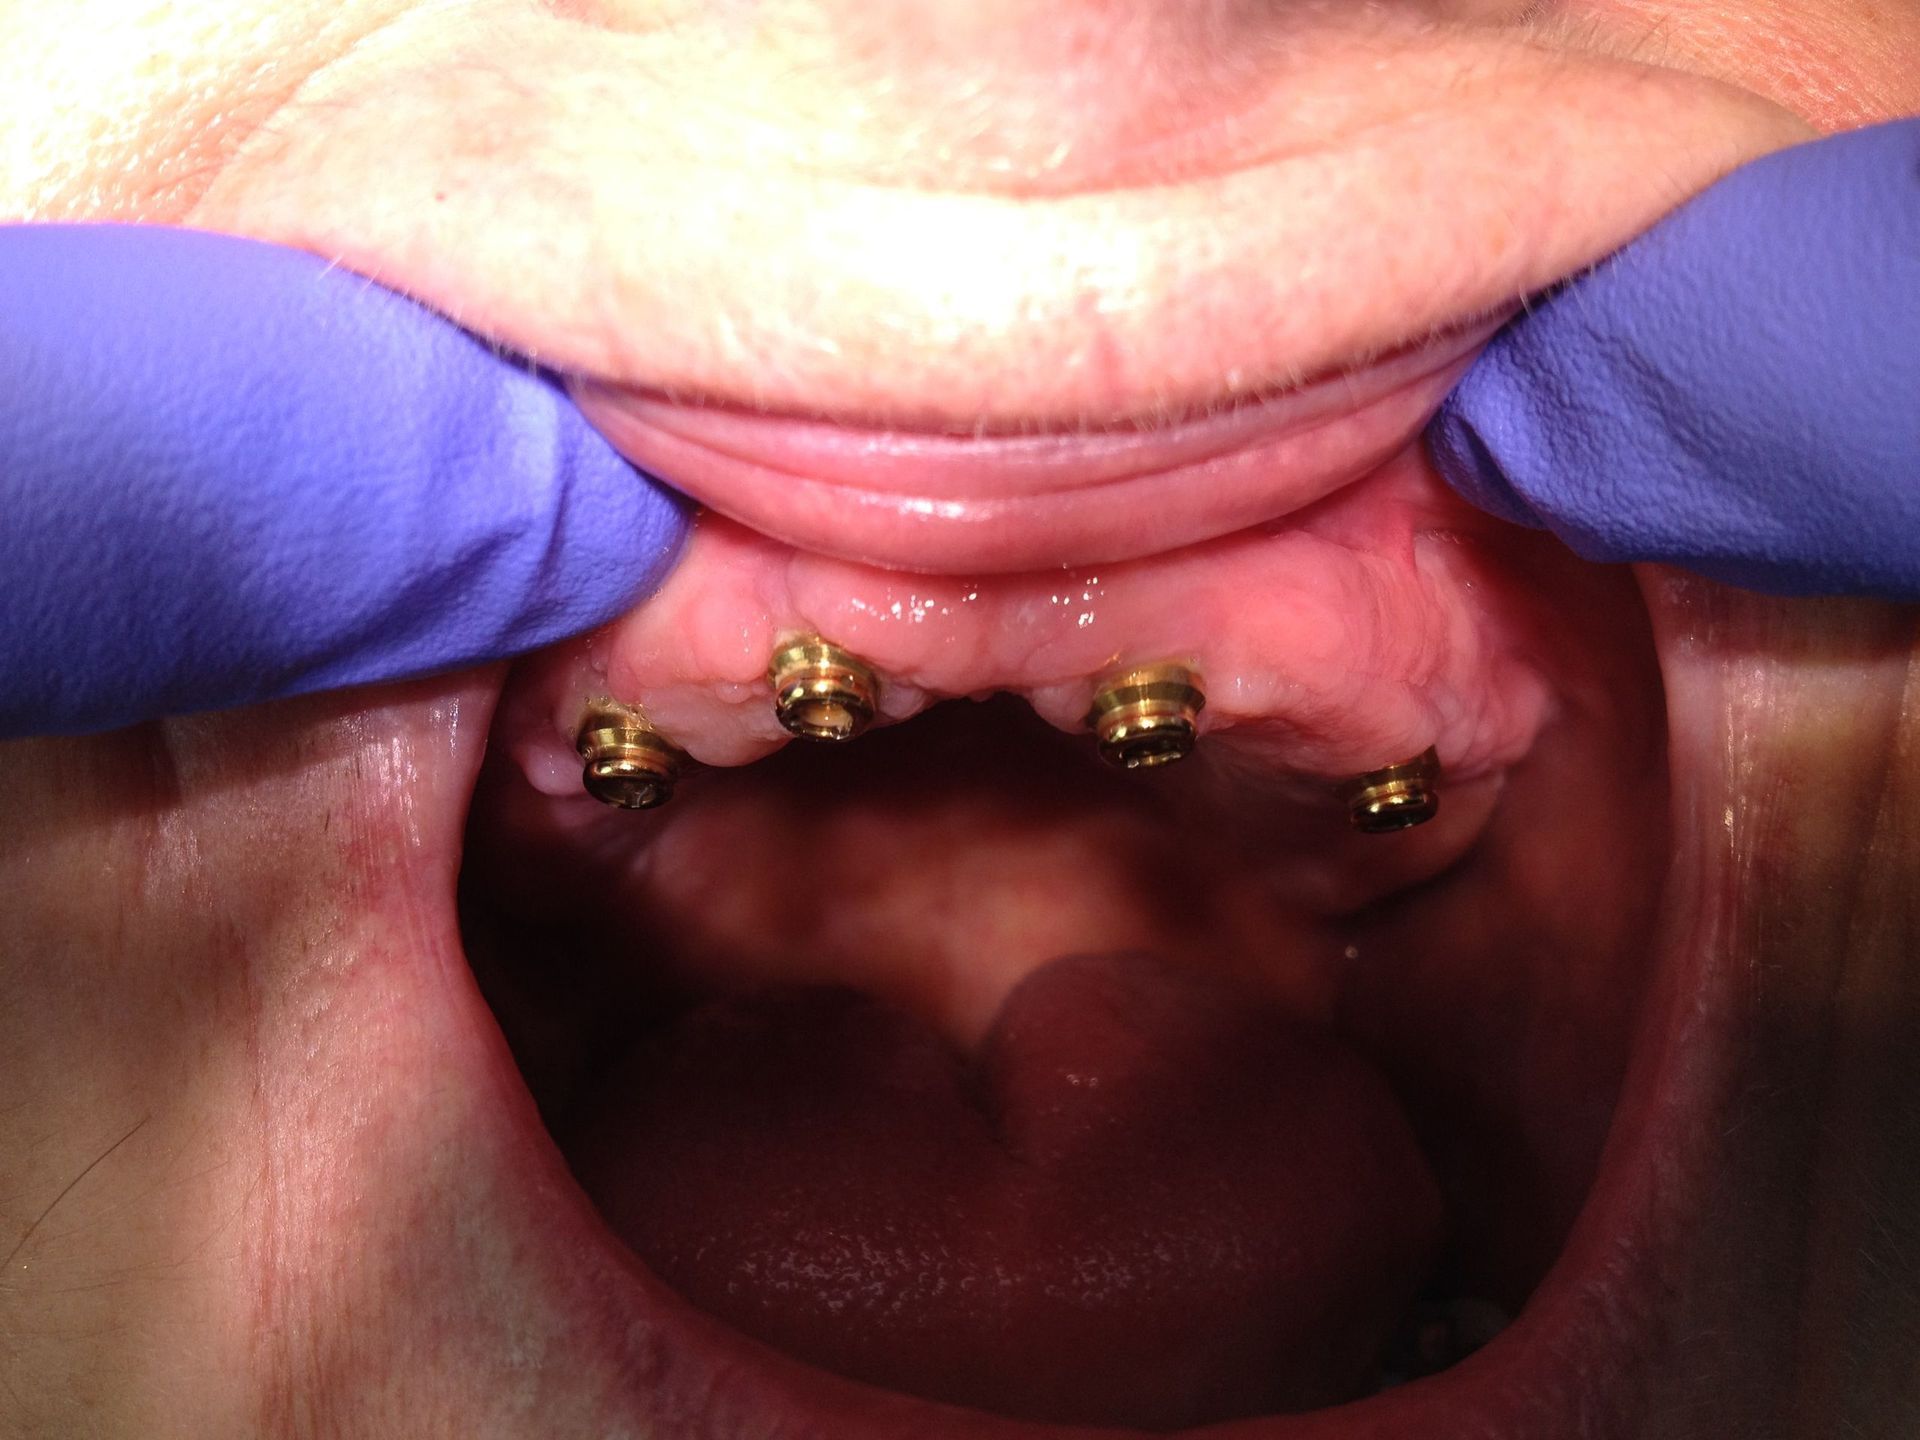

Avant et après implants